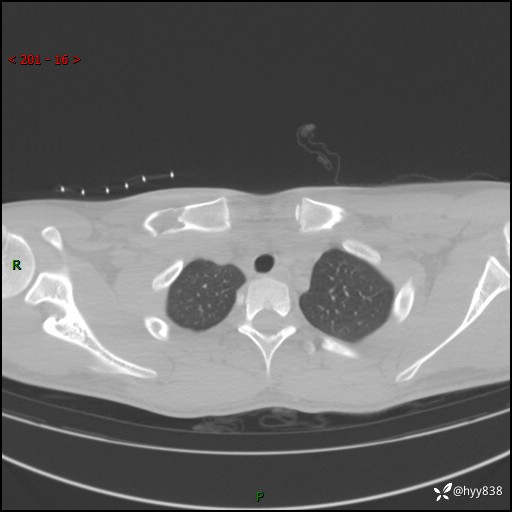

CT